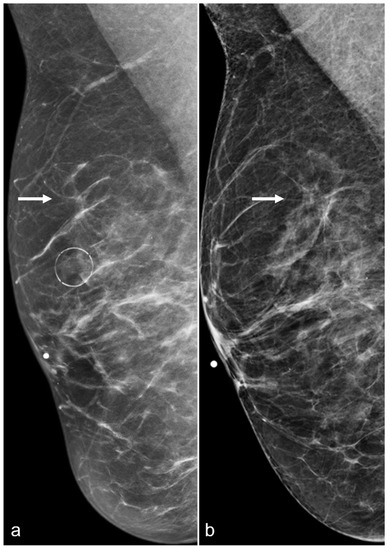

Figure 16. A 52-year-old woman with a history of subglandular silicone implants. Prior mammograms with implant displaced views were negative. A screening mammogram with bilateral CC and MLO views one year after BES (a) demonstrates a spiculated mass in the left lower inner quadrant (arrow), which was biopsied under ultrasound guidance with pathology revealing invasive ductal carcinoma. T1-weighted post-contrast MRI axial images demonstrate areas of fat necrosis in both breasts ((b,c), arrowheads). An enhancing mass with a biopsy clip is seen adjacent to the surgical scar ((c), arrow) in the left breast representing the biopsy proven carcinoma.